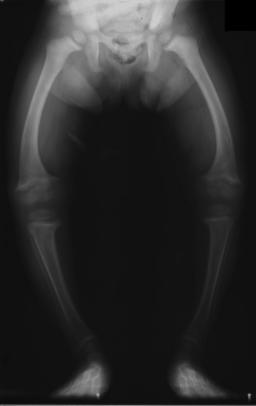

| X-ray of a two-year-old with rickets, with a marked bowing of the femurs and decreased bone density | |

Rickets is a condition that results in weak or soft bones in children, and is caused by either dietary deficiency or genetic causes.[2] Symptoms include bowed legs, stunted growth, bone pain, large forehead, and trouble sleeping.[2][3] Complications may include bone deformities, bone pseudofractures and fractures, muscle spasms, or an abnormally curved spine.[2][3]

Young children may have bowed legs and thickened ankles and wrists;[13] older children may have knock knees.[10] Spinal curvatures of kyphoscoliosis or lumbar lordosis may be present. The pelvic bones may be deformed. A condition known as rachitic rosary can result as the thickening caused by nodules forming on the costochondral joints. This appears as a visible bump in the middle of each rib in a line on each side of the body. This somewhat resembles a rosary, giving rise to its name. The deformity of a pigeon chest[10] may result in the presence of Harrison's groove.

An X-ray or radiograph of an advanced patient with rickets tends to present in a classic way: the bowed legs (outward curve of long bone of the legs) and a deformed chest. Changes in the skull also occur causing a distinctive "square headed" appearance known as "caput quadratum".[14] These deformities persist into adult life if not treated. Long-term consequences include permanent curvatures or disfiguration of the long bones, and a curved back.[15]

Occasionally surgery is needed to correct severe and persistent deformities of the lower limbs, especially around the knees namely genu varum and genu valgum. Surgical correction of rachitic deformities can be achieved through osteotomies or guided growth surgery. Guided growth surgery has almost replaced the use of corrective osteotomies. The functional results of guided growth surgery in children with rickets are satisfactory. While bone osteotomies work through acute/immediate correction of the limb deformity, guided growth works through gradual correction.[7]